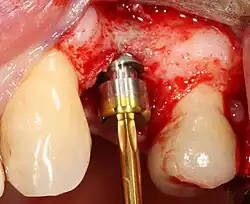

Placing the implant

Most implant systems have five basic steps for placement of each implant:[28]: 214–221

- Soft tissue reflection: An incision is made over the crest of bone, splitting the thicker attached gingiva roughly in half so that the final implant will have a thick band of tissue around it. The edges of tissue, each referred to as a flap, are pushed back to expose the bone. Flapless surgery is an alternate technique, where a small punch of tissue (the diameter of the implant) is removed for implant placement rather than raising flaps.

- Drilling at high speed: After reflecting the soft tissue, and using a surgical guide or stent as necessary, pilot holes are placed with precision drills at highly regulated speed to prevent burning or pressure necrosis of the bone.

- Drilling at low speed: The pilot hole is expanded by using progressively wider drills (typically between three and seven successive drilling steps, depending on implant width and length). Care is taken not to damage the osteoblast or bone cells by overheating. A cooling saline or water spray keeps the temperature low.

- Placement of the implant: The implant screw is placed and can be self-tapping;[50]: 100–102 otherwise, the prepared site is tapped with an implant analog. It is then screwed into place with a torque controlled wrench[54] at a precise torque so as not to overload the surrounding bone (overloaded bone can die, a condition called osteonecrosis, which may lead to failure of the implant to fully integrate or bond with the jawbone).

- Tissue adaptation: The gingiva is adapted around the entire implant to provide a thick band of healthy tissue around the healing abutment. In contrast, an implant can be "buried", where the top of the implant is sealed with a cover screw and the tissue is closed to completely cover it. A second procedure would then be required to uncover the implant at a later date.